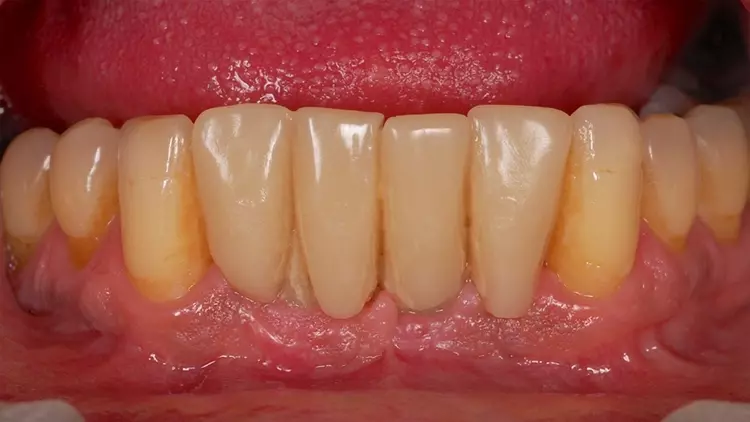

Die Restaurationen fügten sich sowohl klinisch als auch ästhetisch durch ihre spezielle Charakterisierung in die bestehende Patientensituation ein (Abb. 13-15). Auch röntgenologisch konnte eine gute Passform ermittelt werden (Abb. 16).

Der fehlende Zahn 24 wurde ebenfalls mittels eines Semados RS Implantats (BEGO Implant Systems GmbH & Co. KG) mit einer Länge/einem Durchmesser von 4,1/10,0 mm und einer monolithischen Zirkonoxidkrone ersetzt (3D Pro). Die klinische Situation konnte im Rahmen einer Nachuntersuchung im September 2022, fast zweieinhalb Jahre nach der Versorgung im Mai 2020 als sehr gut bezeichnet werden (Abb. 17-20).

Der vorliegende Patientenfall beschreibt die Implantatversorgung im Ober- und Unterkiefer-Frontzahnbereich eines älteren Patienten mit einer chronischen Parodontitis und ohne systemische Erkrankungen bzw. ohne eine regelmäßige Einnahme von Medikamenten. Infolge des Attachmentverlusts konnte trotz einer Ridge Preservation mittels Sofortimplantation und einer bukkalen Auflagerung von xenogenem Knochenersatzmaterial insbesondere im Bereich der Interdentalpapillen des Oberkiefers kein ausreichender Weichgewebserhalt in vertikaler Richtung erzielt werden, was auf den Attachmentverlust infolge der Parodontitis zurückgeführt werden kann. Daher war es notwendig, die fehlenden Papillen mittels rosa eingefärbten Zirkonoxids in die Restauration zu integrieren (Abb. 13 und 14).

Der Patient wurde entsprechend instruiert, diese Bereiche täglich mittels Interdentalbürsten zu reinigen. Rezessionen wurden nicht beobachtet, was auf den dicken Phänotyp des Patienten zurückgeführt werden könnte [5]. Trotz der geringen Einschränkungen im Bereich der rot-weißen Ästhetik war der Patient mit dem ästhetischen Gesamtergebnis zufrieden.